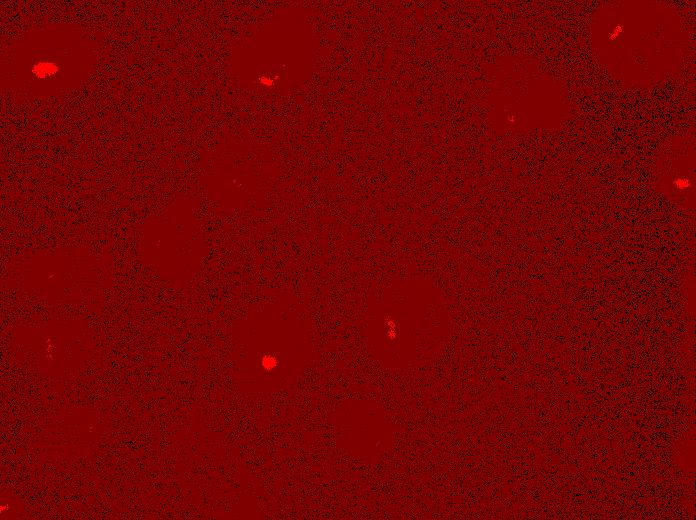

SMAD4